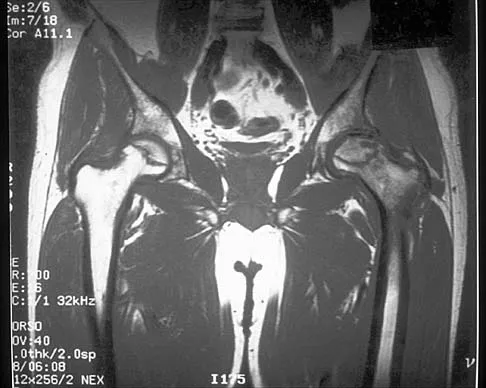

Question 52 High Yield

A 9-year-old child has right groin pain after falling from a tree. Examination reveals that the right leg is held in external rotation, and there is significant pain with attempts at passive range of motion. Radiographs are shown in Figures 43a and 43b. Management should consist of

Detailed Explanation

The complications of femoral neck fractures in children include osteonecrosis, malunion, nonunion, and premature physeal closure. It is presumed that the risk of osteonecrosis is directly related to the amount of displacement at the time of injury and is not affected by the type of treatment. The risk of the other complications can be decreased depending on the type of treatment. Anatomic reduction by either closed or open methods can reduce the risk of malunion. The addition of internal fixation allows for maintenance of the reduction. In young children who cannot comply with a partial or non-weight-bearing status, the addition of a spica cast gives added protection. Canale ST: Fractures of the hip in children and adolescents. Orthop Clin North Am 1990;21:341-352.